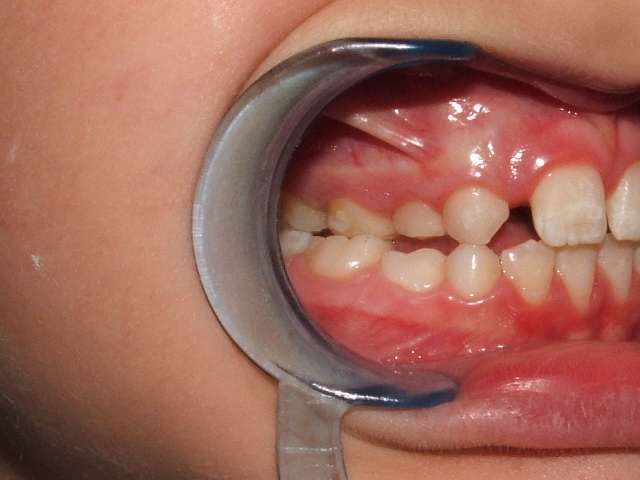

Morso aperto anteriore associato a Cross bite scheletrico